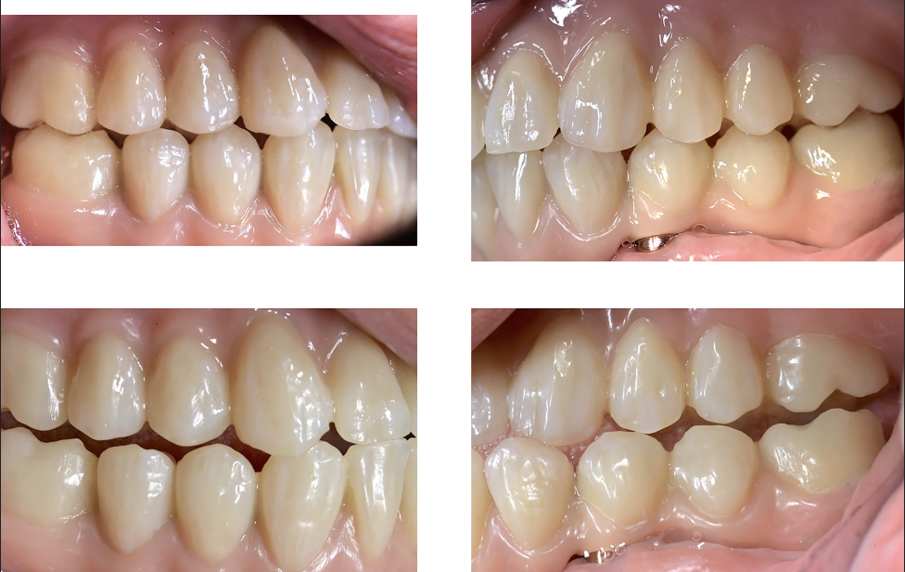

Dopo alcuni mesi, altri quattro impianti sono stati inseriti ai mascellari posteriori utilizzando la stessa guida chirurgica (Fig. 23), e dopo altri sei mesi l’arcata superiore era pronta per essere caricata con una riabilitazione protesica fissa su impianti. Tutte le procedure dell’arcata inferiore sono state ripetute per l’arcata superiore (Figg. 24, 25), perfezionando l’ADSD e controllando l’accuratezza dei contatti occlusali.